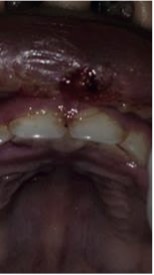

Figura 2. Examen intraoral.

Al examen intraoral (Figura 2) se observan múltiples lesiones vesiculares y ampollares en labio superior e inferior, úlceras mayores y menores en cara dorsal de la lengua y en paladar duro, sin ningún tipo de tratamiento.